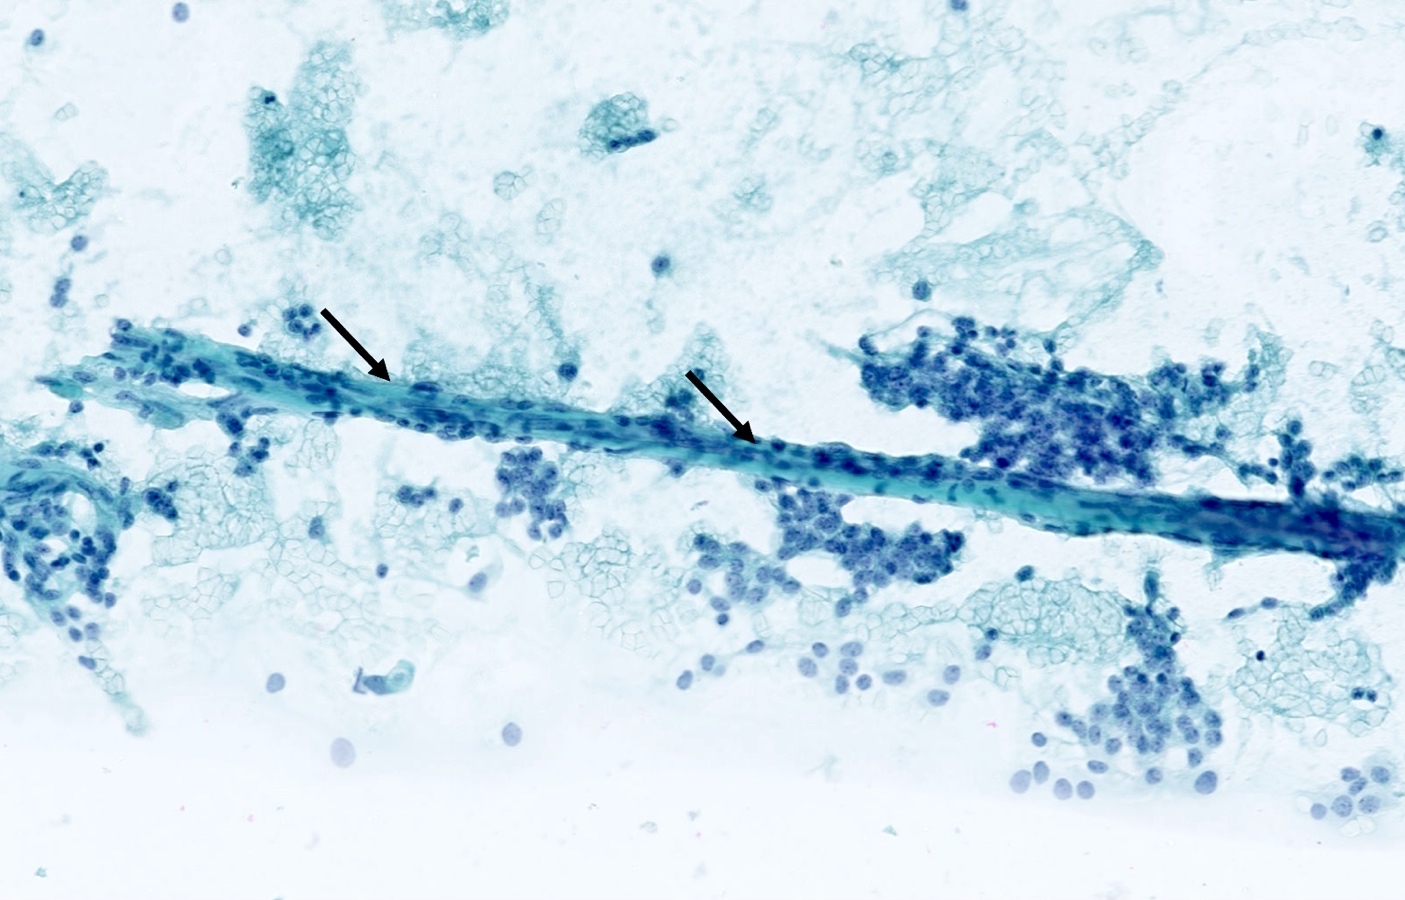

Cytology description

- Loosely cohesive groups and isolated cells sometimes around branching capillaries; rosette structures may be seen (Cibas: Cytology - Diagnostic Principles and Clinical Correlates, 4th Edition, 2014)

- Uniform population of small tumor cells with round / elongated or plasmacytoid shape

- Smooth nuclear outlines, uniform with salt and pepper chromatin and a small nucleolus; no or rare mitoses

- Scant granular cytoplasm

- Absence of molding, nuclear crush and necrosis

Cytology images